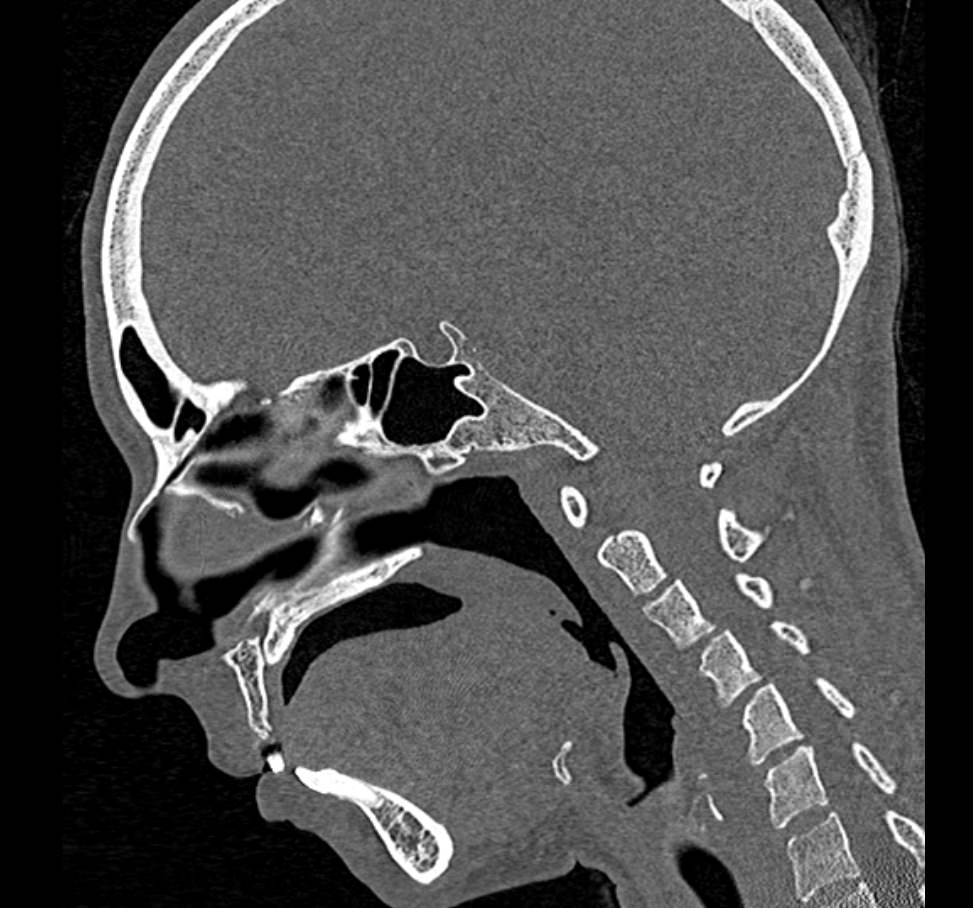

Мультиспиральная компьютерная томография относится к высокоинформативным лучевым методам исследования, то есть основана на применении рентгеновского излучения и различной способности тканей поглощать рентгеновские лучи. Костные структуры обладают наибольшей плотностью по сравнению с другими тканями, поэтому в большей степени поглощают рентгеновские лучи и лучше всего визуализируются при данном исследовании. Благодаря этому КТ позволяет детально изучить кости лицевого черепа, а также углубления, которые являются вместилищем для важных органов (глазницы, полость носа, ротовая полость).

КТ мягких тканей лица является наиболее информативным методом диагностики травматических повреждений лица, посттравматических деформаций, аномалий развития, инородных предметов в носовой полости и околоносовых пазухах. Кроме того, мультиспиральная КТ применяется для выявления скрытых воспалительных процессов, нарушений кровообращения в области лица, а также используется при планировании оперативного вмешательства (в том числе, пластических операций) и в дальнейшем применяется в послеоперационном периоде для оценки успешности проведенной операции.

Детальные изображения костей лицевого черепа и мягких тканей лица получаются за счет вращения трубки томографа с излучателями рентгеновских лучей вокруг объекта исследования. В аппаратах увеличено количество сверхчувствительных детекторов, позволяющих производить множество послойных снимков с толщиной среза от 0,5 мм, которые затем преобразуются в трехмерные пространственные модели лицевого черепа с окружающими тканями. Такие инновационные возможности аппаратов обеспечивают проведение точной и достоверной диагностики.